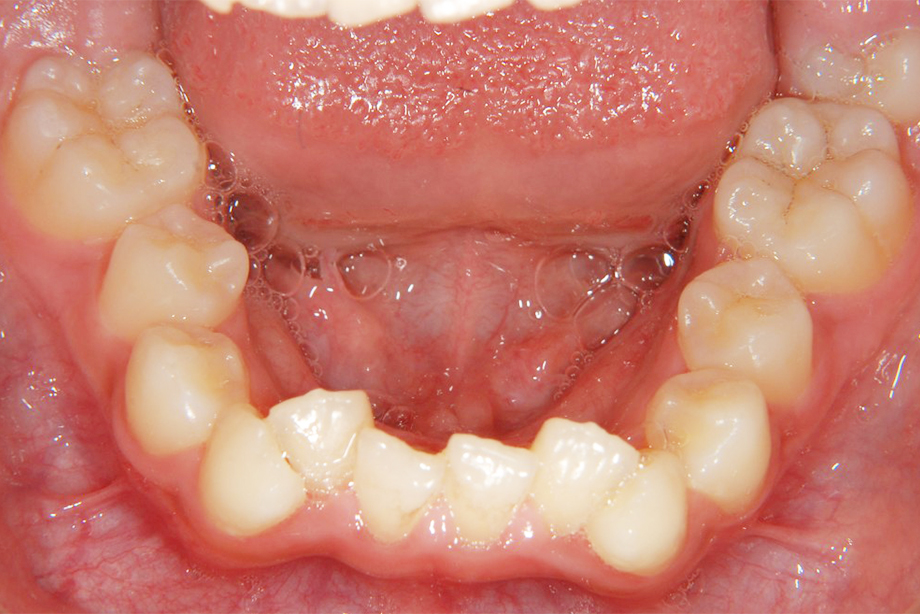

第Ⅰ期治療

乳歯、もしくは乳歯と永久歯が混ざっている時期の治療です。歯の治療というよりも、顎の骨の成長を促したり、歯並びに影響を与える筋機能の訓練などを行います。

- 矯正後